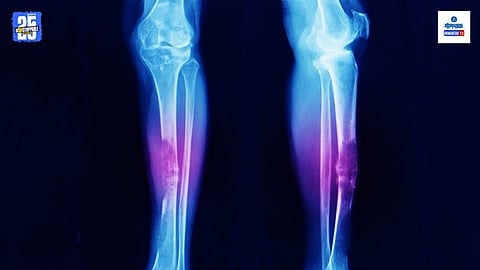

हाडांच्या कर्करोगाचे अनेक प्रकार आहेत. जेव्हा कर्करोगाच्या पेशी हाडांमध्ये वाढतात तेव्हा त्या हाडांच्या पेशींना नुकसान पोहोचवतात. हाडांच्या कर्करोगाला हाडांचा सारकोमा असेही म्हणतात. हा कर्करोग मांडीचे हाड, पिंडरीच्या हाडात होतो. शरीराच्या इतर भागांचा कर्करोग हाडांमध्ये पसरतो तसाच हाडांचा कर्करोग देखील शरीराच्या इतर भागात पसरु शकतो.

दरम्यान, जेव्हा हाडांचा कर्करोग (Cancer) होतो तेव्हा त्याची लक्षणे सहसा सुरुवातीला दिसून येत नाहीत. ज्यामुळे सुरुवातीच्या टप्प्यात या आजाराची तीव्रता कळत नाही. हाडांचा कर्करोग गंभीर असतो आणि त्यावर तात्काळ उपचारांची आवश्यकता असते. बऱ्याच प्रकरणांमध्ये, जर वेळेवर उपचार केले तर तो पूर्णपणे बरा होऊ शकतो. हाडांच्या कर्करोगाचे प्रामुख्याने तीन प्रकार आहेत. हे ऑस्टियोसारकोमा, कॉन्ड्रोसारकोमा आणि कॉर्डोमा आहेत. याशिवाय, फायब्रो सारकोमा देखील आहे. सुरुवातीला काही लोकांमध्ये या कर्करोगाची लक्षणे दिसून येतात.

दिल्लीतील राजीव गांधी कॅन्सर हॉस्पिटलमधील मेडिकल ऑन्कोलॉजीचे एचओडी डॉ. विनीत तलवार सांगतात की, हाडांचा कर्करोग झाल्यावर सुरुवातीला काही लक्षणे दिसून येतात, यामध्ये हाडांच्या वेदनांचा समावेश आहे. चालताना किंवा हात वर करताना वेदना जाणवणे, सांध्यामध्ये वेदना जाणवणे. सांधेदुखी बहुतेकदा रात्री जाणवते. याशिवाय, कोणत्याही प्रकारची क्रिया करताना वेदना जाणवू शकतात. यासोबतच, प्रभावित भागात गाठीला सूज येऊ शकते, ज्यामुळे तुम्हाला अस्वस्थ वाटू शकते. याशिवाय, हाडे कमकुवत होतात आणि किरकोळ दुखापतीनेही ती तुटतात. याशिवाय, थकवा आणि वजन कमी होणे ही देखील त्याची लक्षणे असू शकतात.